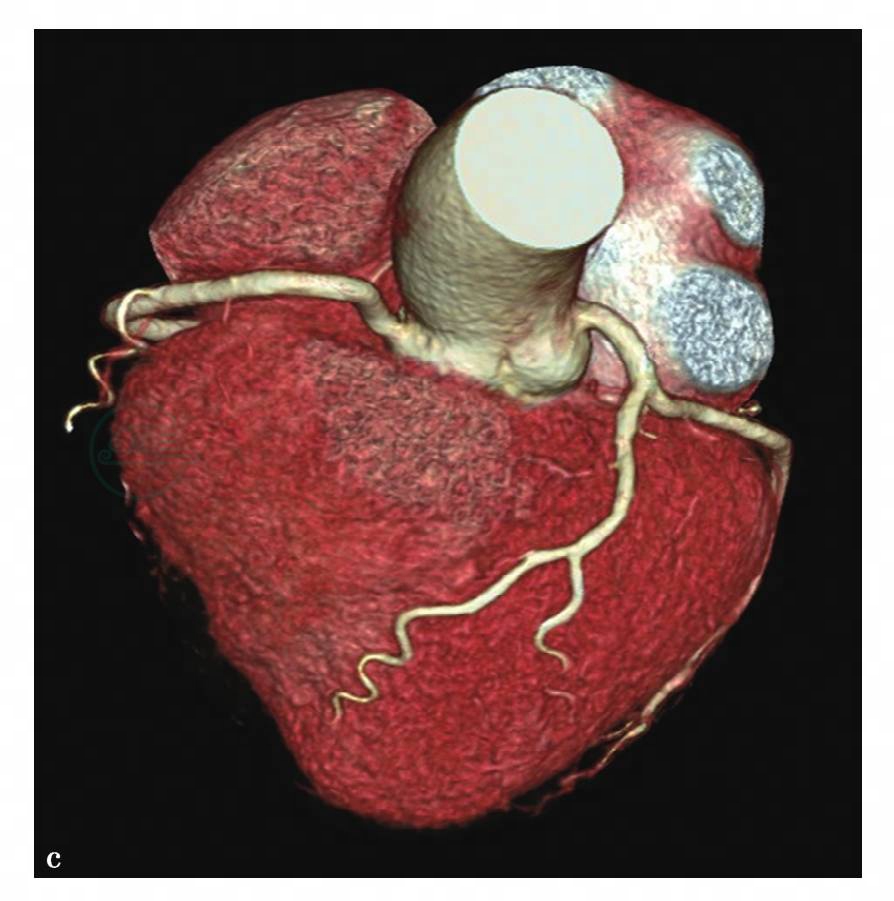

图4 c,心脏CT容积再现图像示冠状动脉未见明显狭窄征象